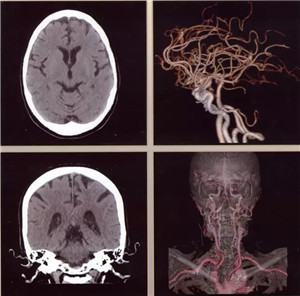

扫描范围最大:16厘米宽体宝石探测器,心脏、颅脑、肝脏等单器官检查一次扫描就可实现全覆盖;

图像分辨超清:0.23毫米的空间分辨率,对于2毫米冠脉支架的细节和支架内再狭窄清晰可辨;可超早期发现微小肿瘤病变。